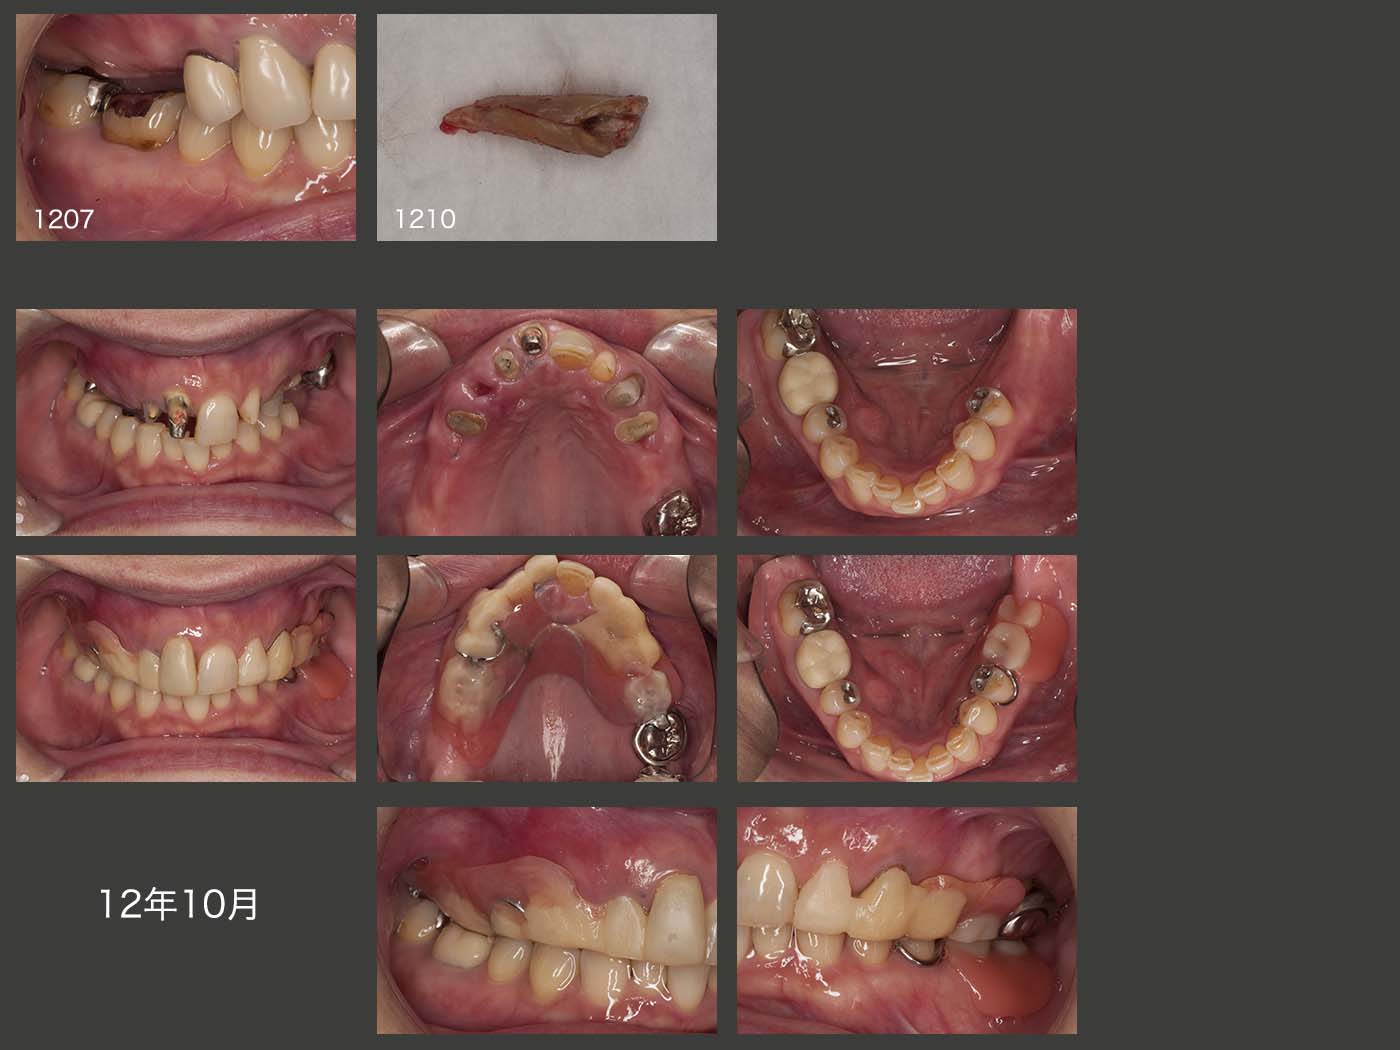

右上6(移植歯)の経過.まずスライド左上は,2013年5月,クラウン装着時の状態であるが,特に問題はない.しかし,15年11月,初診終了時においては,近心に歯周ポケットが7mmあり,デンタルX線写真から近心に透過像が認められる.16年9月の時点では,歯周ポケットが近心で10mmとなったため,クラウンを除去し,力の解放を行った.17年1月に,歯周外科を行い,今度はコーヌス冠を装着して,2次固定効果を期待した.(17年9月装着,歯周ポケットは5mmに回復した.)しかし,18年2月,右上4のコアごと脱離の際,移植歯を精査したところ,頰側歯肉縁下に炎症性吸収が生じ,歯質がなくなっていた.そこをさらに深く追っていくと,上顎洞の穿孔も認められたため,抜去せざるを得なかった.もちろん私の手技が稚拙であることは間違いないが,ここが偏咀嚼主機能歯になったことが大きな要因になったことも否定できない.18年3月,右上4に根面板を装着した.

その後,20年9月,右上2を歯根破折で抜去した.10月,左下の義歯を誤って排水溝に落とし,紛失.左下5に内冠の上からクラウンを装着した.いずれ上顎は総義歯になるという川の流れは変えられないと思うが,下顎の残存歯は両側犬歯が有髄歯でもあるから,上顎シングルデンチャーでも何とか対応できると考えている.